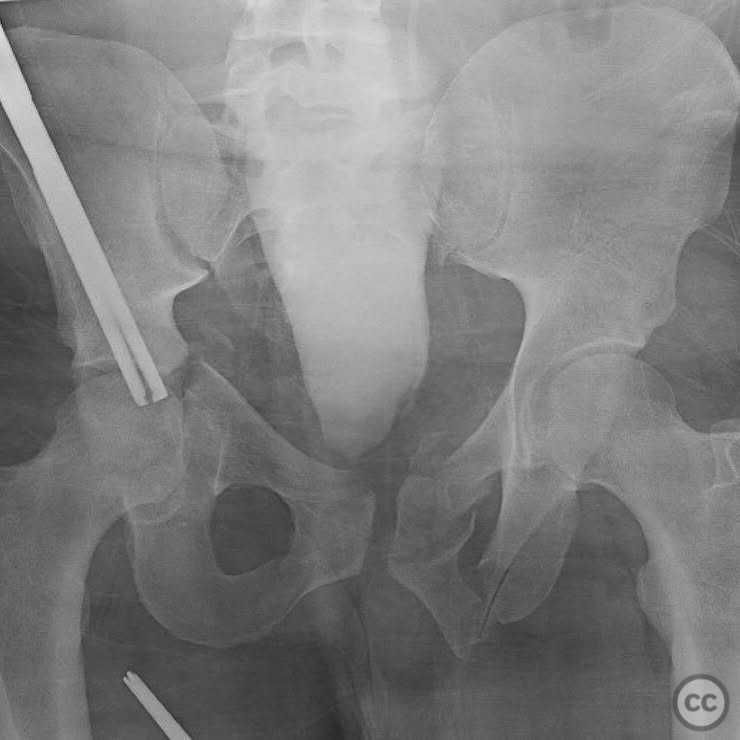

Clinical and radiological findings:  The patient presented with a highly unstable pelvic ring injury and a transverse acetabulum fracture, accompanied by a bladder injury. The bladder injury was addressed emergently with a low vertical midline Pfannenstiel incision for repair, followed by the placement of a low right-sided suprapubic catheter. Radiological imaging confirmed the transverse acetabular fracture and disruption of the left sacroiliac joint, along with a displaced sacral fracture.

Planning remarks:  The preoperative plan involved a staged approach to address the combined injuries. Initially, the focus was on stabilizing the pelvic ring to provide a stable base for subsequent acetabular reconstruction. The left sacroiliac joint disruption was to be reduced and stabilized first, followed by lag screw fixation of the displaced sacral fracture. Additional screws were planned as anatomical corridors allowed. An external fixator was considered to support the posterior ring stabilization. The second stage involved open reduction and internal fixation (ORIF) of the acetabulum through a Kocher-Langenbeck approach, with potential anterior column fixation via the modified Stoppa approach if necessary.